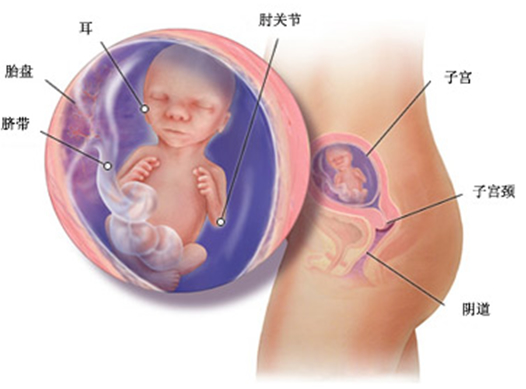

此时胎儿的头已占全身长的 1/3,头部及身体上呈现出一层薄薄的胎毛,白色的脂肪逐渐覆盖皮肤。手指脚趾长出指甲,并呈现出隆起,耳朵的入口张开;牙床开始形成;头发、眉毛齐备;由于皮下脂肪开始沉积,皮肤变成半透明,但皮下血管仍清晰可见;骨骼和肌肉也越来越结实。

如果是一个女婴,则阴道已发育成形。

身长已增长到 18—25 里面左右,体重大约 250—300 克,已是一个正常足月儿的二分之一了。